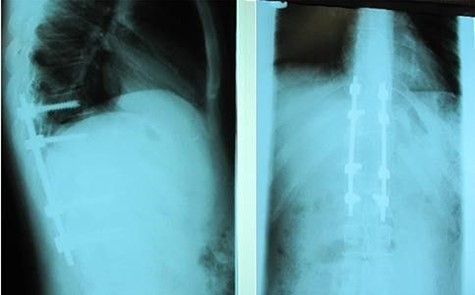

A 24-year-old male presented with acute low back pain with no prior traumatic events. Physical examination was unremarkable except for tenderness over the lower thoracic spine. The laboratory tests including complete blood count, renal function tests, alkaline phosphatase, aspartate aminotransferase, alanine aminotransferase, serum calcium, serum phosphorus and parathyroid hormone were all within normal limits. Initially, the patient was treated conservatively but the pain did not improve. Lumbar X-ray showed mild height loss and fracture of the superior endplate of T12 vertebra (Fig. 1). Computed tomography (CT) showed a multi-lobulated osteolytic lesion within the T12 body with extension to the right pedicle and transverse process (Fig. 2). Magnetic resonance imaging (MRI) revealed a well-defined lesion with low signal intensity on T1 and high signal intensity on T2 weighted images (Fig. 3). The bone scan showed a cold spot at the site of the lesion. The patient underwent surgery and excisional biopsy through the posterior approach. A large clear fluid-filled cavity was curetted and the cavity was filled with an autologous bone graft from iliac crest. Posterior spinal fusion was performed with instrumentation with pedicle screws from T10 to L2 and a mixture of autologous bone graft and allograft was used to achieve better fusion (Fig. 4). Pathology report confirmed the diagnosis of SBC and the patient received no further treatment (Fig. 5). The patient had no recurrence in 10-year follow up.